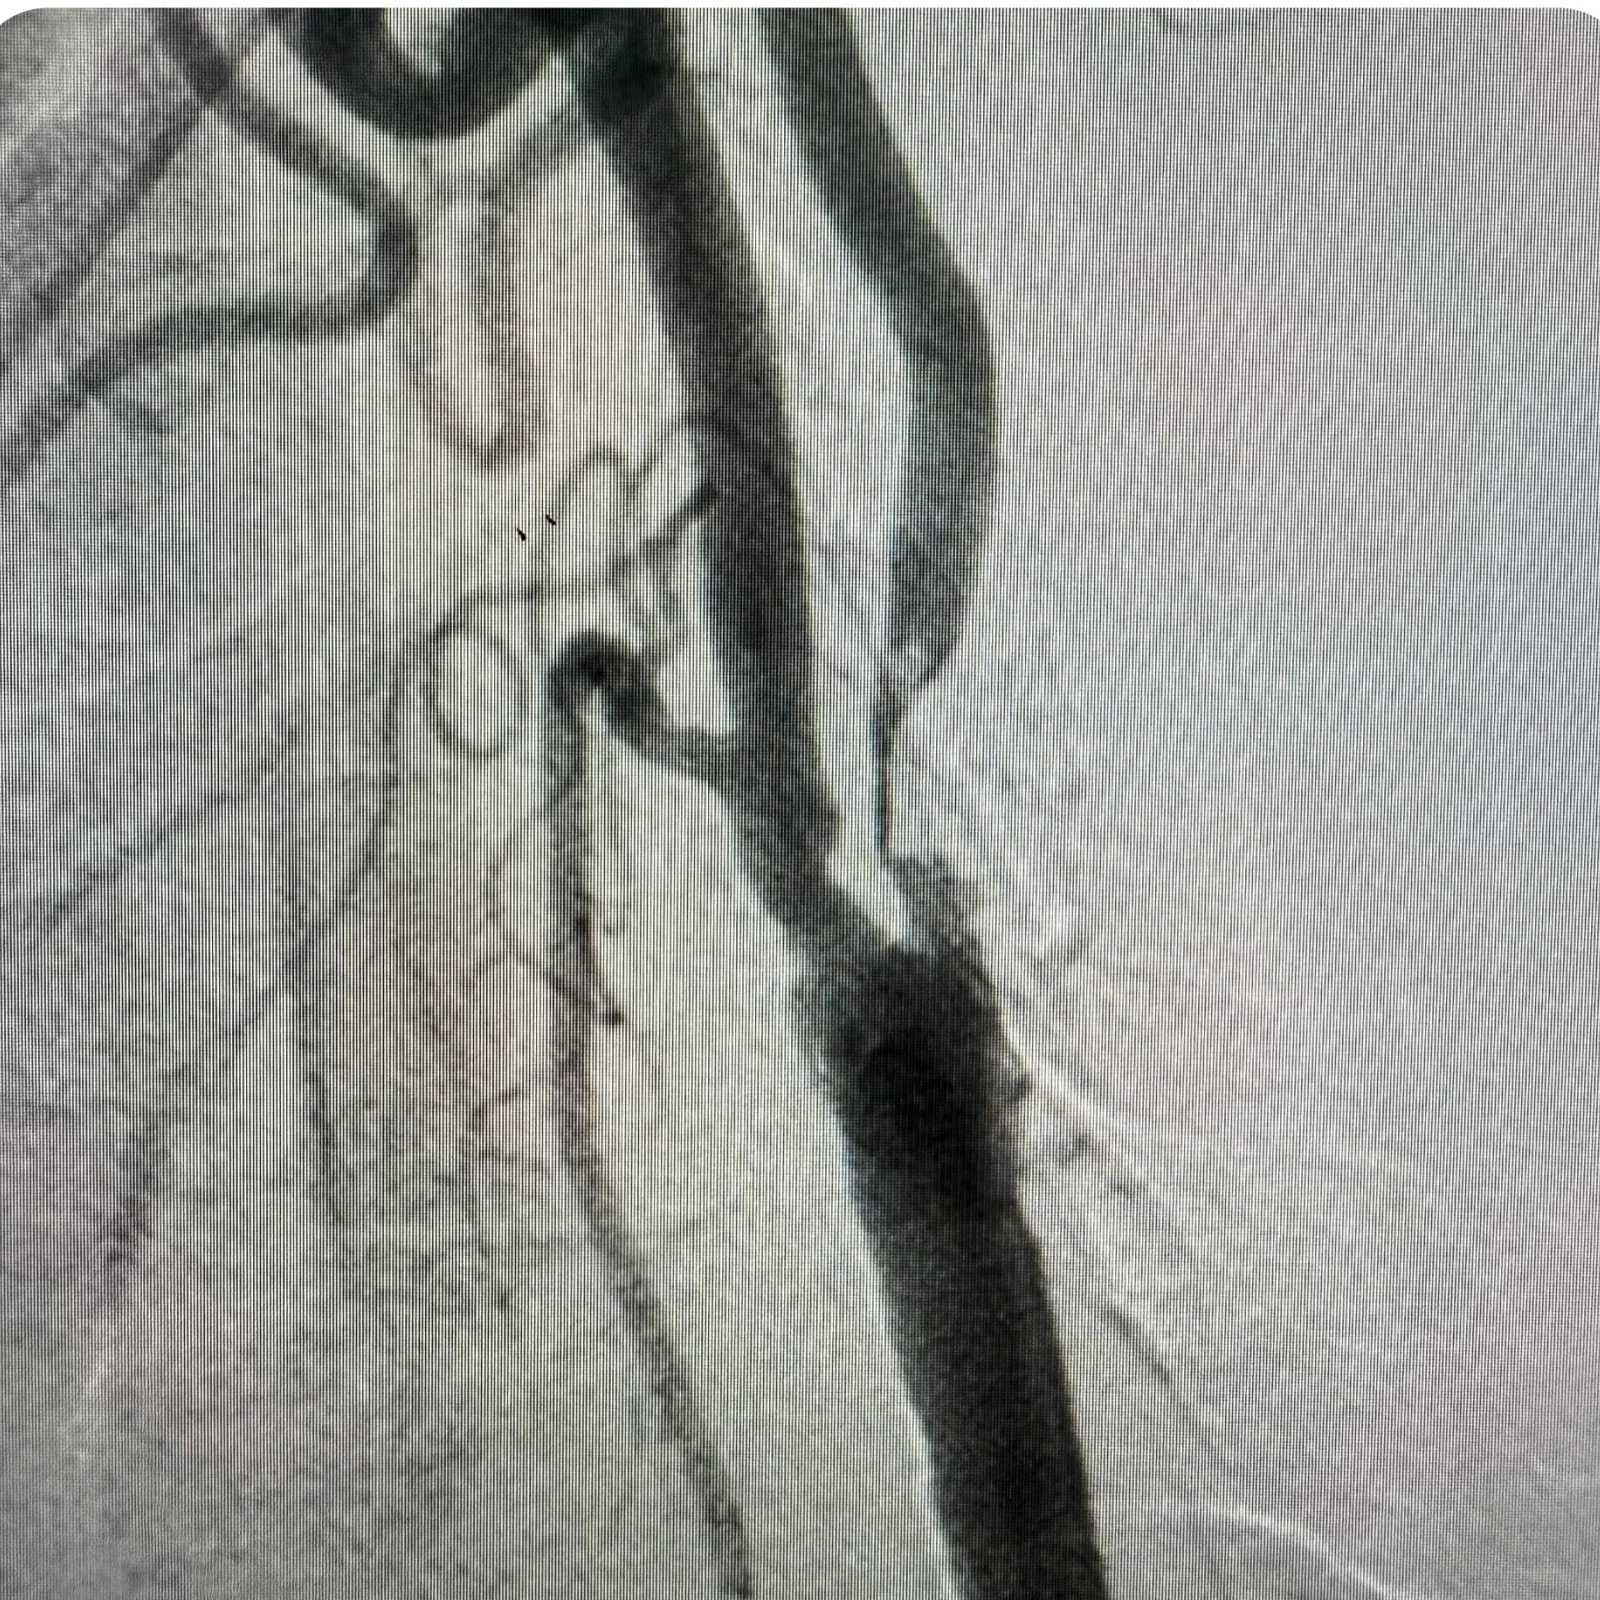

Селективна субтракційна ангіографія (DSA, Digital Subtraction Angiography) — це сучасний метод візуалізації судин, який дозволяє отримати чіткі зображення артерій і вен без “зашумлення” від навколишніх тканин.

Процедура проводиться за допомогою контрастного введення через катетер в конкретну судину, а спеціальна технологія субтракції “віднімає” фонові структури, залишаючи лише кровоносні судини на зображенні.

• Ангіопластика та стентування артерій

• Відновлення кровотоку при стенозах або оклюзіях периферичних та магістральних судин

• Коронарографія — рентгенконтрастне дослідження коронарних артерій для виявлення звужень або оклюзій